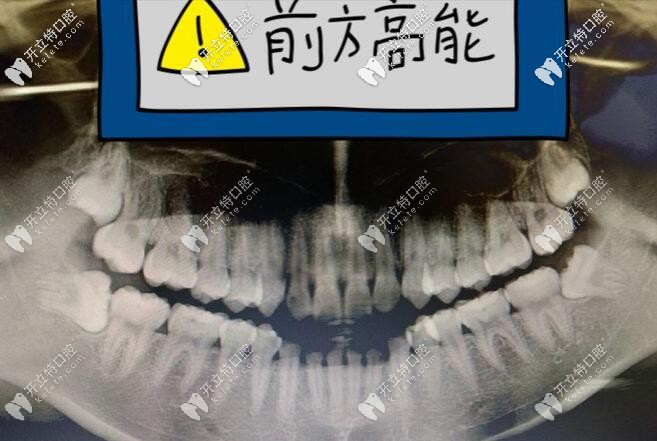

拔牙時(shí)候的感受如下圖:

一個(gè)醫(yī)生+兩個(gè)助理圍著我,就有一種莫名的緊張感;過程就不詳述了,總之就是撬啊,還有掰啊,有一種拔樹的感覺,但是自己沒啥感覺。